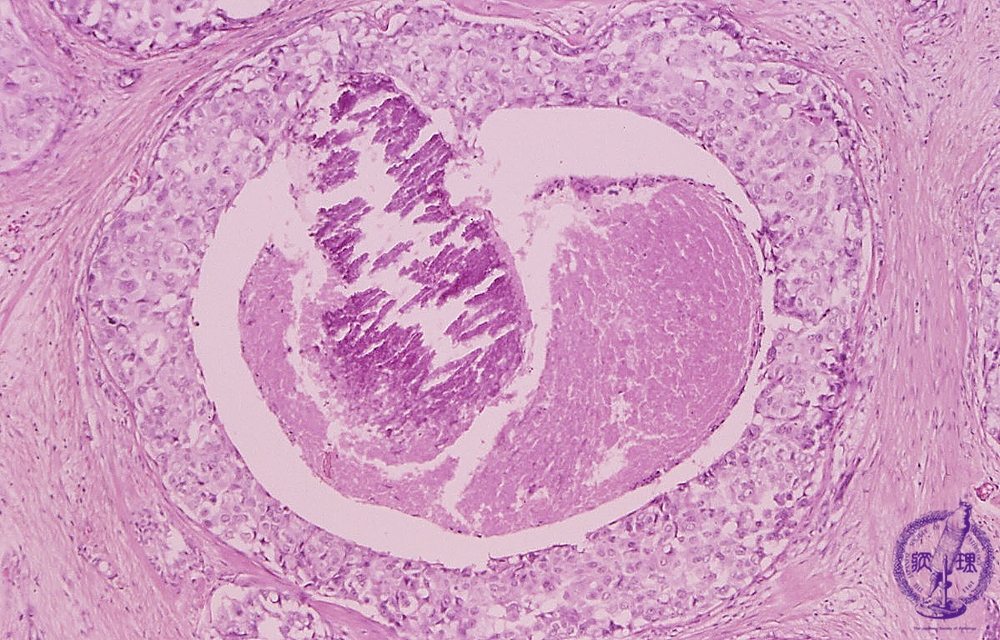

- ★(5)noninvasive carcinoma (comedo type)

Microscopic image(HE stain, high power view):Large carcinoma cells piled up to several layers filling ductal lumen (arrow). Central necrosis and necrotic calcification (dotted line) are also apparant.